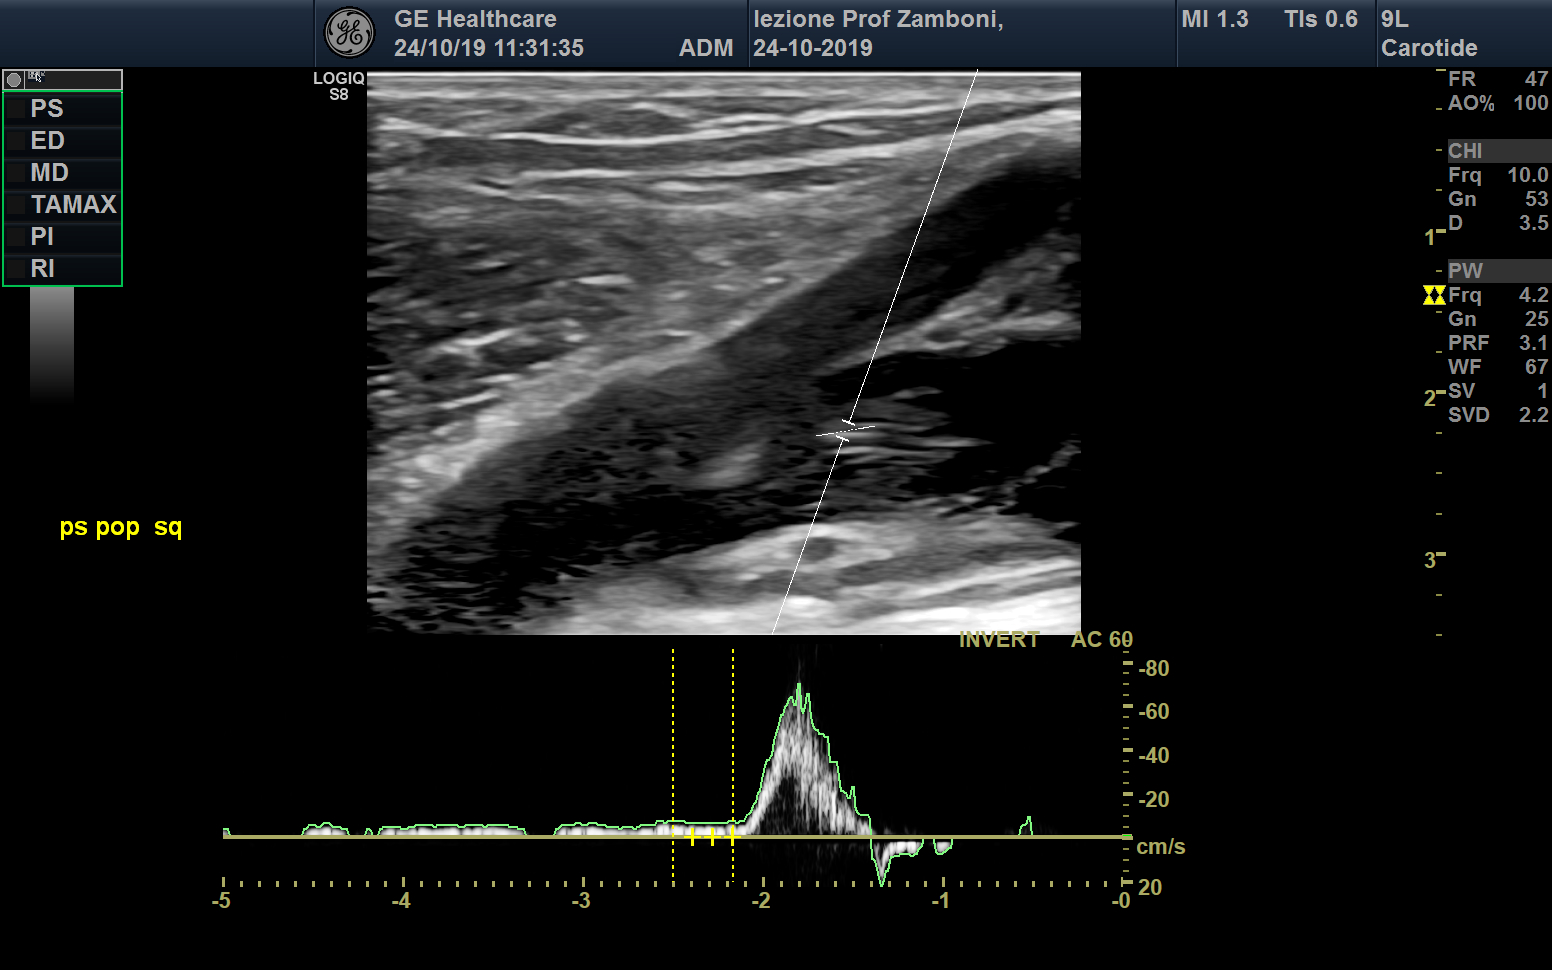

PW V. Poplitea Squizing

JPEG image icon PW V. Poplitea Squizing.jpg — JPEG image, 504 kB (516970 bytes)